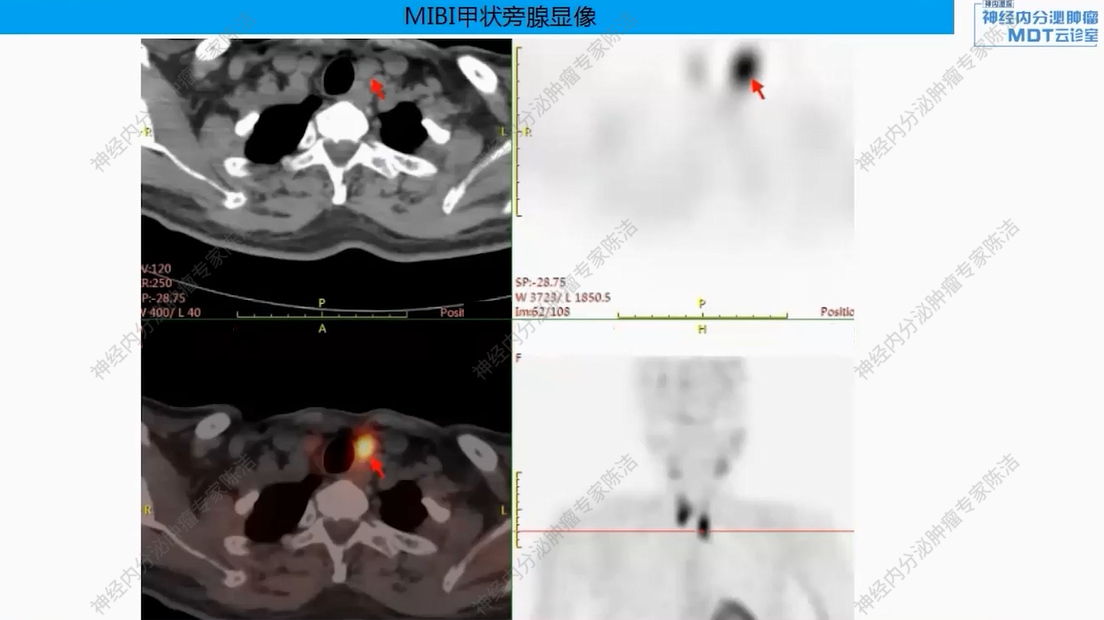

影像学:垂体MRI提示垂体稍大,最厚9mm,未见明显结节。MIBI甲状旁腺显像提示甲状腺双叶下后方软组织密度影,考虑甲状旁腺瘤,多发骨质改变。

核医学科徐俊彦教授:本病例双扫描PET显像体现了该患者多发肿瘤间异质性。胰尾大病灶(胰岛素瘤)呈SSTR阴性、FDG阳性,这符合约50%胰岛素瘤不表达SSTR的特征。而胰体小病灶呈SSTR阳性、FDG轻度增高。垂体区在SSTR(有生理性摄取)和FDG(无生理性摄取)上均呈阳性,提示垂体瘤可能。骨骼病灶呈SSTR和FDG“双阳性”,高度提示为SSTR阳性的NET转移,但建议对于骨病灶,可对相对表浅的病灶行骨穿以进一步明确骨病灶情况。从最初影像可见髂骨存在明显骨质破坏,甚至骨皮质整体受损,因此骨转移的可能性较大。然而,鉴于该患者同时患有甲状旁腺瘤,甲状旁腺瘤常伴发棕色瘤改变,故目前不能排除甲状旁腺继发的骨改变的可能。

头颈外科王宇教授:在甲状旁腺病灶的处理上,该患者表现出较高的PTH水平(2200+),但术后血钙水平持续正常(约2.4 mmol/L)。怀疑临床检测到的高水平PTH可能是无生物活性的激素片段,而非全长的活性PTH。也可能是患者使用双磷酸盐后高钙血症得以控制。因此,患者虽然有甲状旁腺瘤,但目前血钙正常,可暂不对甲状旁腺进行手术干预。

后续治疗需要明确多发骨质改变的性质,建议对骨病灶进行穿刺活检。此举旨在鉴别其究竟是SSTR阳性的NET骨转移,还是甲状旁腺病变相关的骨病。若证实为SSTR阳性的NET转移,可考虑使用小剂量长效生长抑素类似物进行治疗。若证实为甲旁亢相关骨病,或活检未见肿瘤细胞,则无需使用生长抑素类似物。关于甲状旁腺处理,患者目前无明显血钙升高,可暂不手术,密切随访血钙、PTH变化。对于垂体处理,建议完善垂体薄层动态增强MRI以明确诊断,并评估对周围组织器官压迫情况。